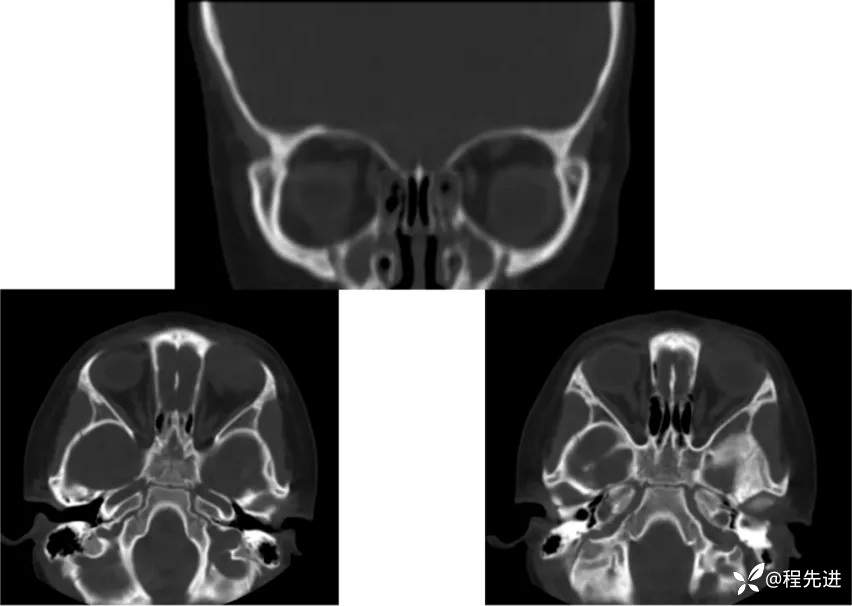

CT平扫: